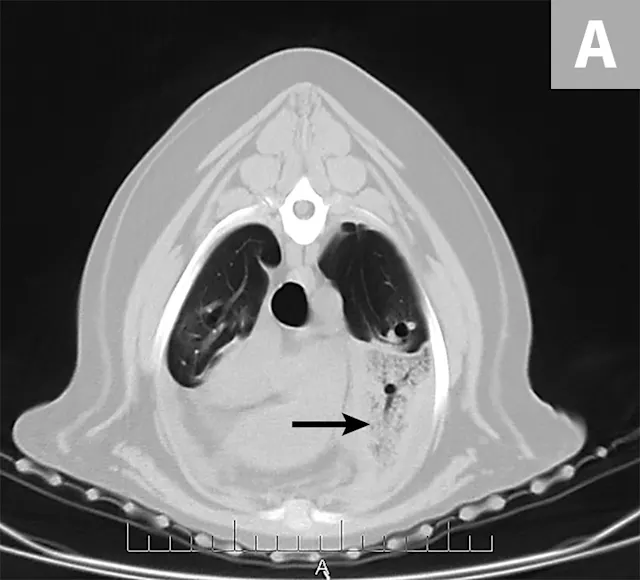

Right lateral thoracic radiographs revealed a large amount of fluid/soft tissue opacity obscuring the cardiac silhouette. Ventrodorsal radiographs showed increased soft tissue opacity in the left hemithorax, primarily in the cranial and middle lung fields. A mild interstitial pattern, a pleural fissure line, and border effacement of the heart were noted in the left hemithorax (Figure 1).

FIGURE 1A

Right lateral (A) and ventrodorsal (B) thoracic radiographs obtained prior to thoracocentesis demonstrating a mild interstitial pattern, moderate pleural effusion, soft tissue opacity in the left cranial and middle lung field, border effacement of the heart, and a pleural fissure line (arrows)